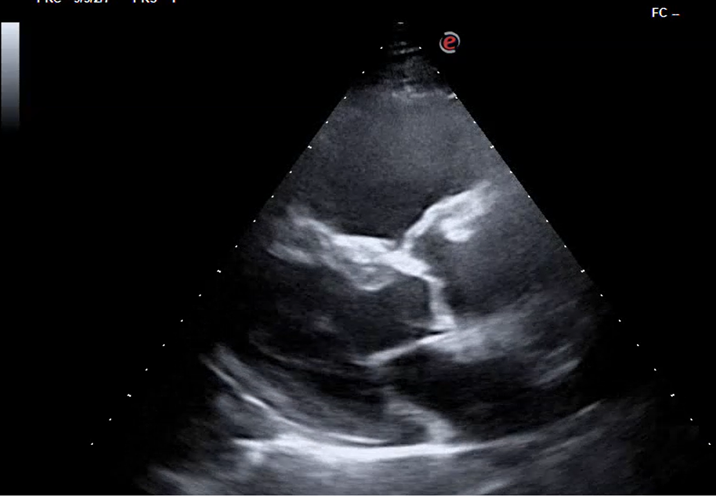

1. Hombre de 82 años que durante consulta de revisión tras caída evidenciamos disnea y taquipnea: TEP agudo bilateral central.